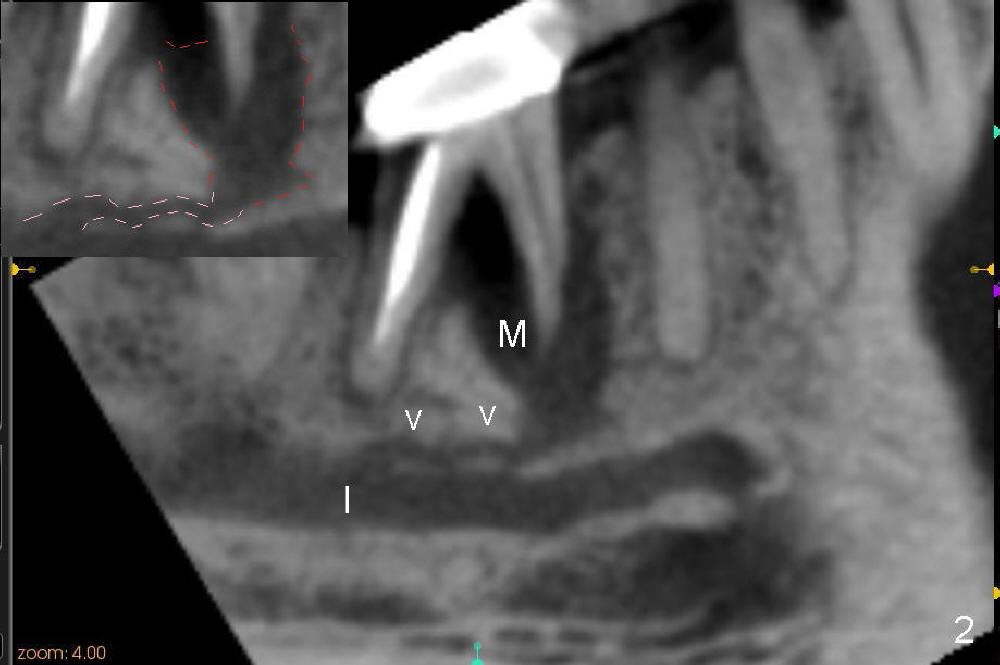

The tooth #30 of a 64-year-old man has endo failure with large radiolucency in the mesial socket (Fig.1 (PA), 2 (CT)). The tooth is nonsalvageable. The mesial lesion is closer to the inferior alveolar nerve (I/IAN) than the distal apex. In addition, there is a connection (Fig.1,2 arrowheads and Fig.2 insert pink dashed line) between the mesial lesion and the nerve. What is the connection, as related to extraction and immediate implant?